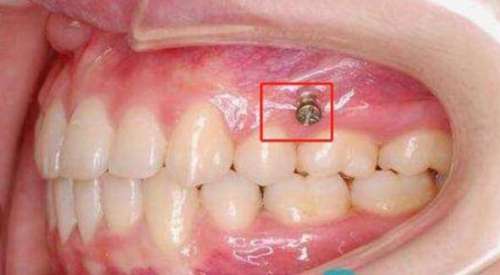

打骨釘是指在手術(shù)中將一根金屬釘子穿過(guò)病人頜骨,在外部固定器的幫助下,強(qiáng)制矯正頜骨的錯(cuò)位,并保持正確的位置。這種方法在調(diào)節(jié)骨性嘴凸方面有著廣泛的應(yīng)用。

打骨釘是將金屬釘子通過(guò)手術(shù)的方式打進(jìn)骨骼中,然后通過(guò)緊固器將釘子與其他金屬部件連接在一起,以固定斷骨或者矯正骨骼的位置。打骨釘?shù)姆绞椒譃閮?nèi)固定和外固定兩種,內(nèi)固定是指將釘子直接打進(jìn)骨骼內(nèi)部,而外固定則是將骨釘釘在骨外部,通過(guò)金屬桿或者線條將骨骼固定住。